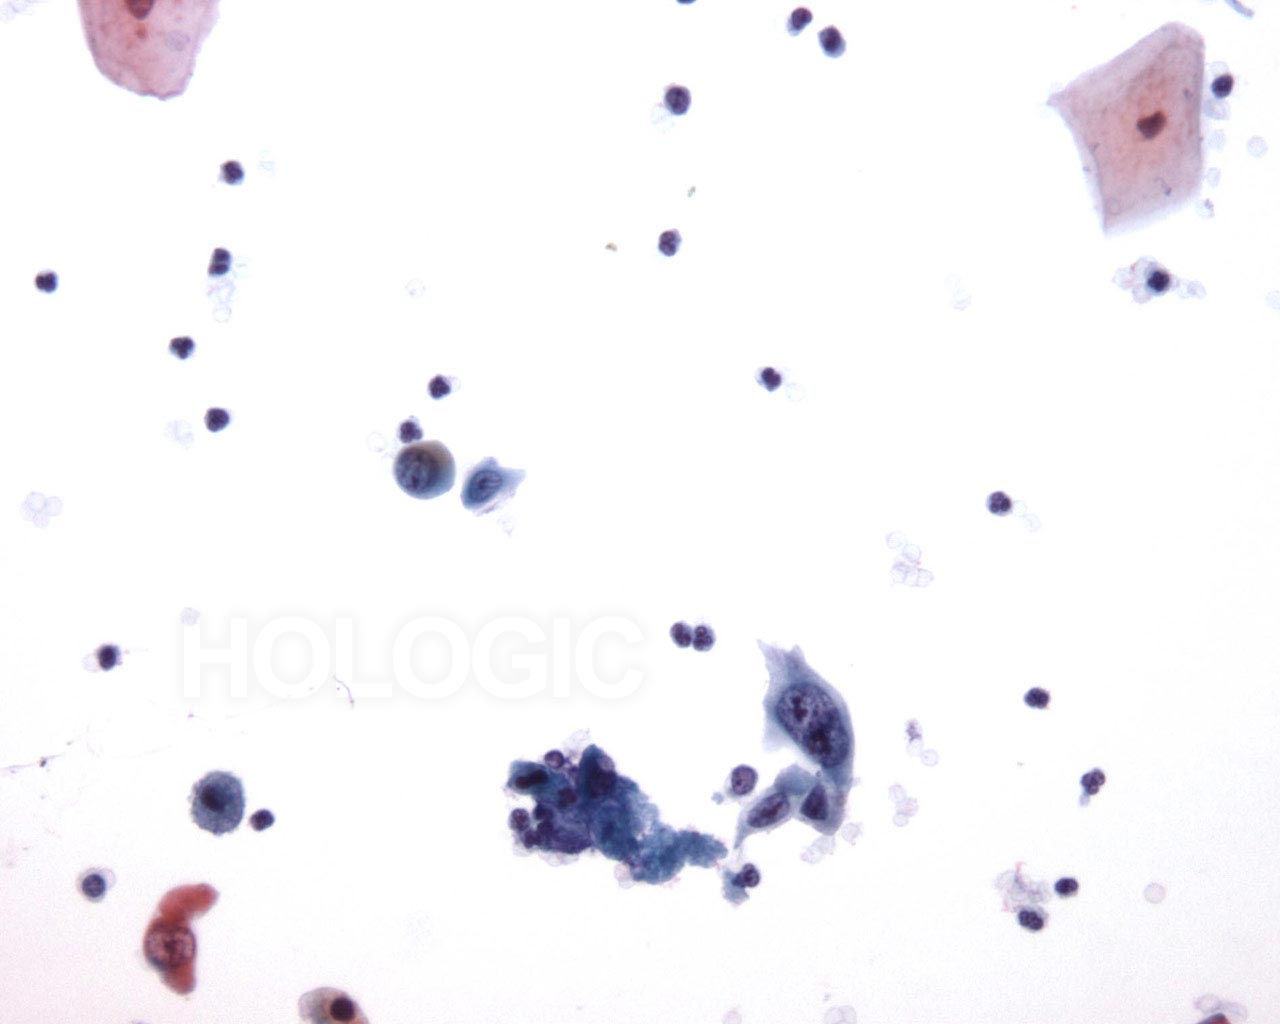

Bronchiale spoeling

Dit cluster bevat abnormale cellen. Hun kerndetail wordt waargenomen in de periferie van het cluster.

20x

Als ze in een cluster liggen, kan het moeilijk zijn de cellen te onderscheiden van plaveiselcelccarcinoom van adenocarcinoom.